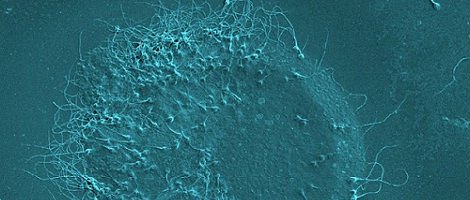

O processo de IAC consiste na estimulação suave e controlada da mulher com o objectivo de que esta produza mais do que um óvulo e na selecção, feita em laboratório, dos melhores espermatozóides do parceiro. Os espermatozóides escolhidos são inseridos numa cánula e introduzidos no útero da mulher quando esta está ovulando. Desta forma as probabilidades de fertilização do óvulo são maiores.